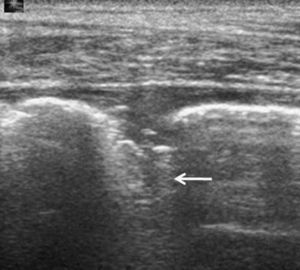

El grosor de la pleura normal es de 0,2–0,4mm. Estas medidas están por debajo de la resolución de los aparatos de ecografía. Así pues, ambas hojas pleurales aparecen en la ecografía como una línea hiperecogénica única que se mueve con la respiración (deslizamiento pulmonar o lung sliding).

La ausencia de artefactos de cola de cometa33 y de deslizamiento pulmonar34,35 —este último signo tanto en escala de grises como con Doppler-color—, la existencia de reverberaciones lineales posteriores33 y la imagen de punto de pulmón (lung point)36 permiten el diagnóstico de neumotórax. El signo del punto de pulmón permite, además, predecir la necesidad de drenaje del neumotórax: cuando su localización es lateral, un 90% de los pacientes necesita drenaje, frente al 8% de los casos en que la localización es anterior32. Los primeros estudios publicados se realizaron en pacientes con traumatismos37,38 o con ventilación mecánica32, aunque los mejores resultados se han obtenido en las series de pacientes a quienes se practica una punción transtorácica, con unos valores de sensibilidad superiores a los de la radiografía convencional y cercanos a los de la TC39,40. Sin embargo, hay falsos positivos, como los descritos en pacientes con enfermedad pulmonar obstructiva crónica (EPOC)41, que presentan una disminución del movimiento pulmonar probablemente condicionada por la hiperinsuflación, si bien esta hipótesis aún no ha sido demostrada. Los pacientes con antecedentes de pleurodesis, afectación pleural por exposición al asbesto o distrés respiratorio agudo también pueden presentar abolición del movimiento pulmonar33. Otra posible limitación de la técnica se encuentra en los pacientes con traumatismo que presenten enfisema subcutáneo, ya que, como se ha mencionado anteriormente, los ultrasonidos sufren una gran atenuación en su propagación por medio aéreo.